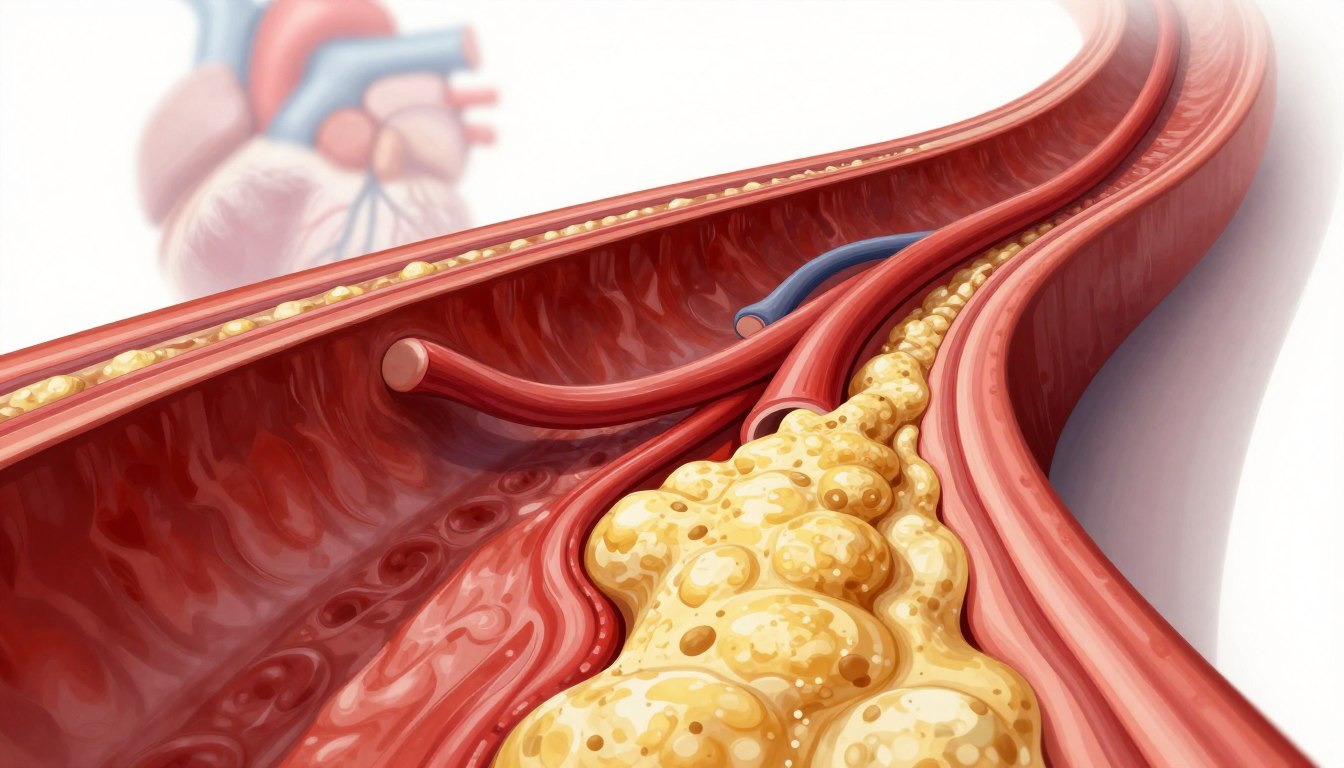

Understanding the Mechanics of Arterial Plaque Buildup

What is Atherosclerosis?

Atherosclerosis means your arteries get clogged with fatty stuff. It starts when cholesterol particles stick to your artery walls. Your body sees this as a threat and sends white blood cells to fight it.

This fight creates inflammation. Over time, cholesterol and immune cells build up, forming plaque. This buildup can block blood flow to your organs.

The Progression of Artery Narrowing

As plaque builds up, your blood vessels get smaller. This artery narrowing makes your heart work harder. At first, the plaque is soft and unstable, which is risky.

If these soft plaques burst, your body tries to heal by forming blood clots. These clots can block blood flow, causing emergencies. Knowing how atherosclerosis works helps you see why it’s crucial to act early and live healthily.